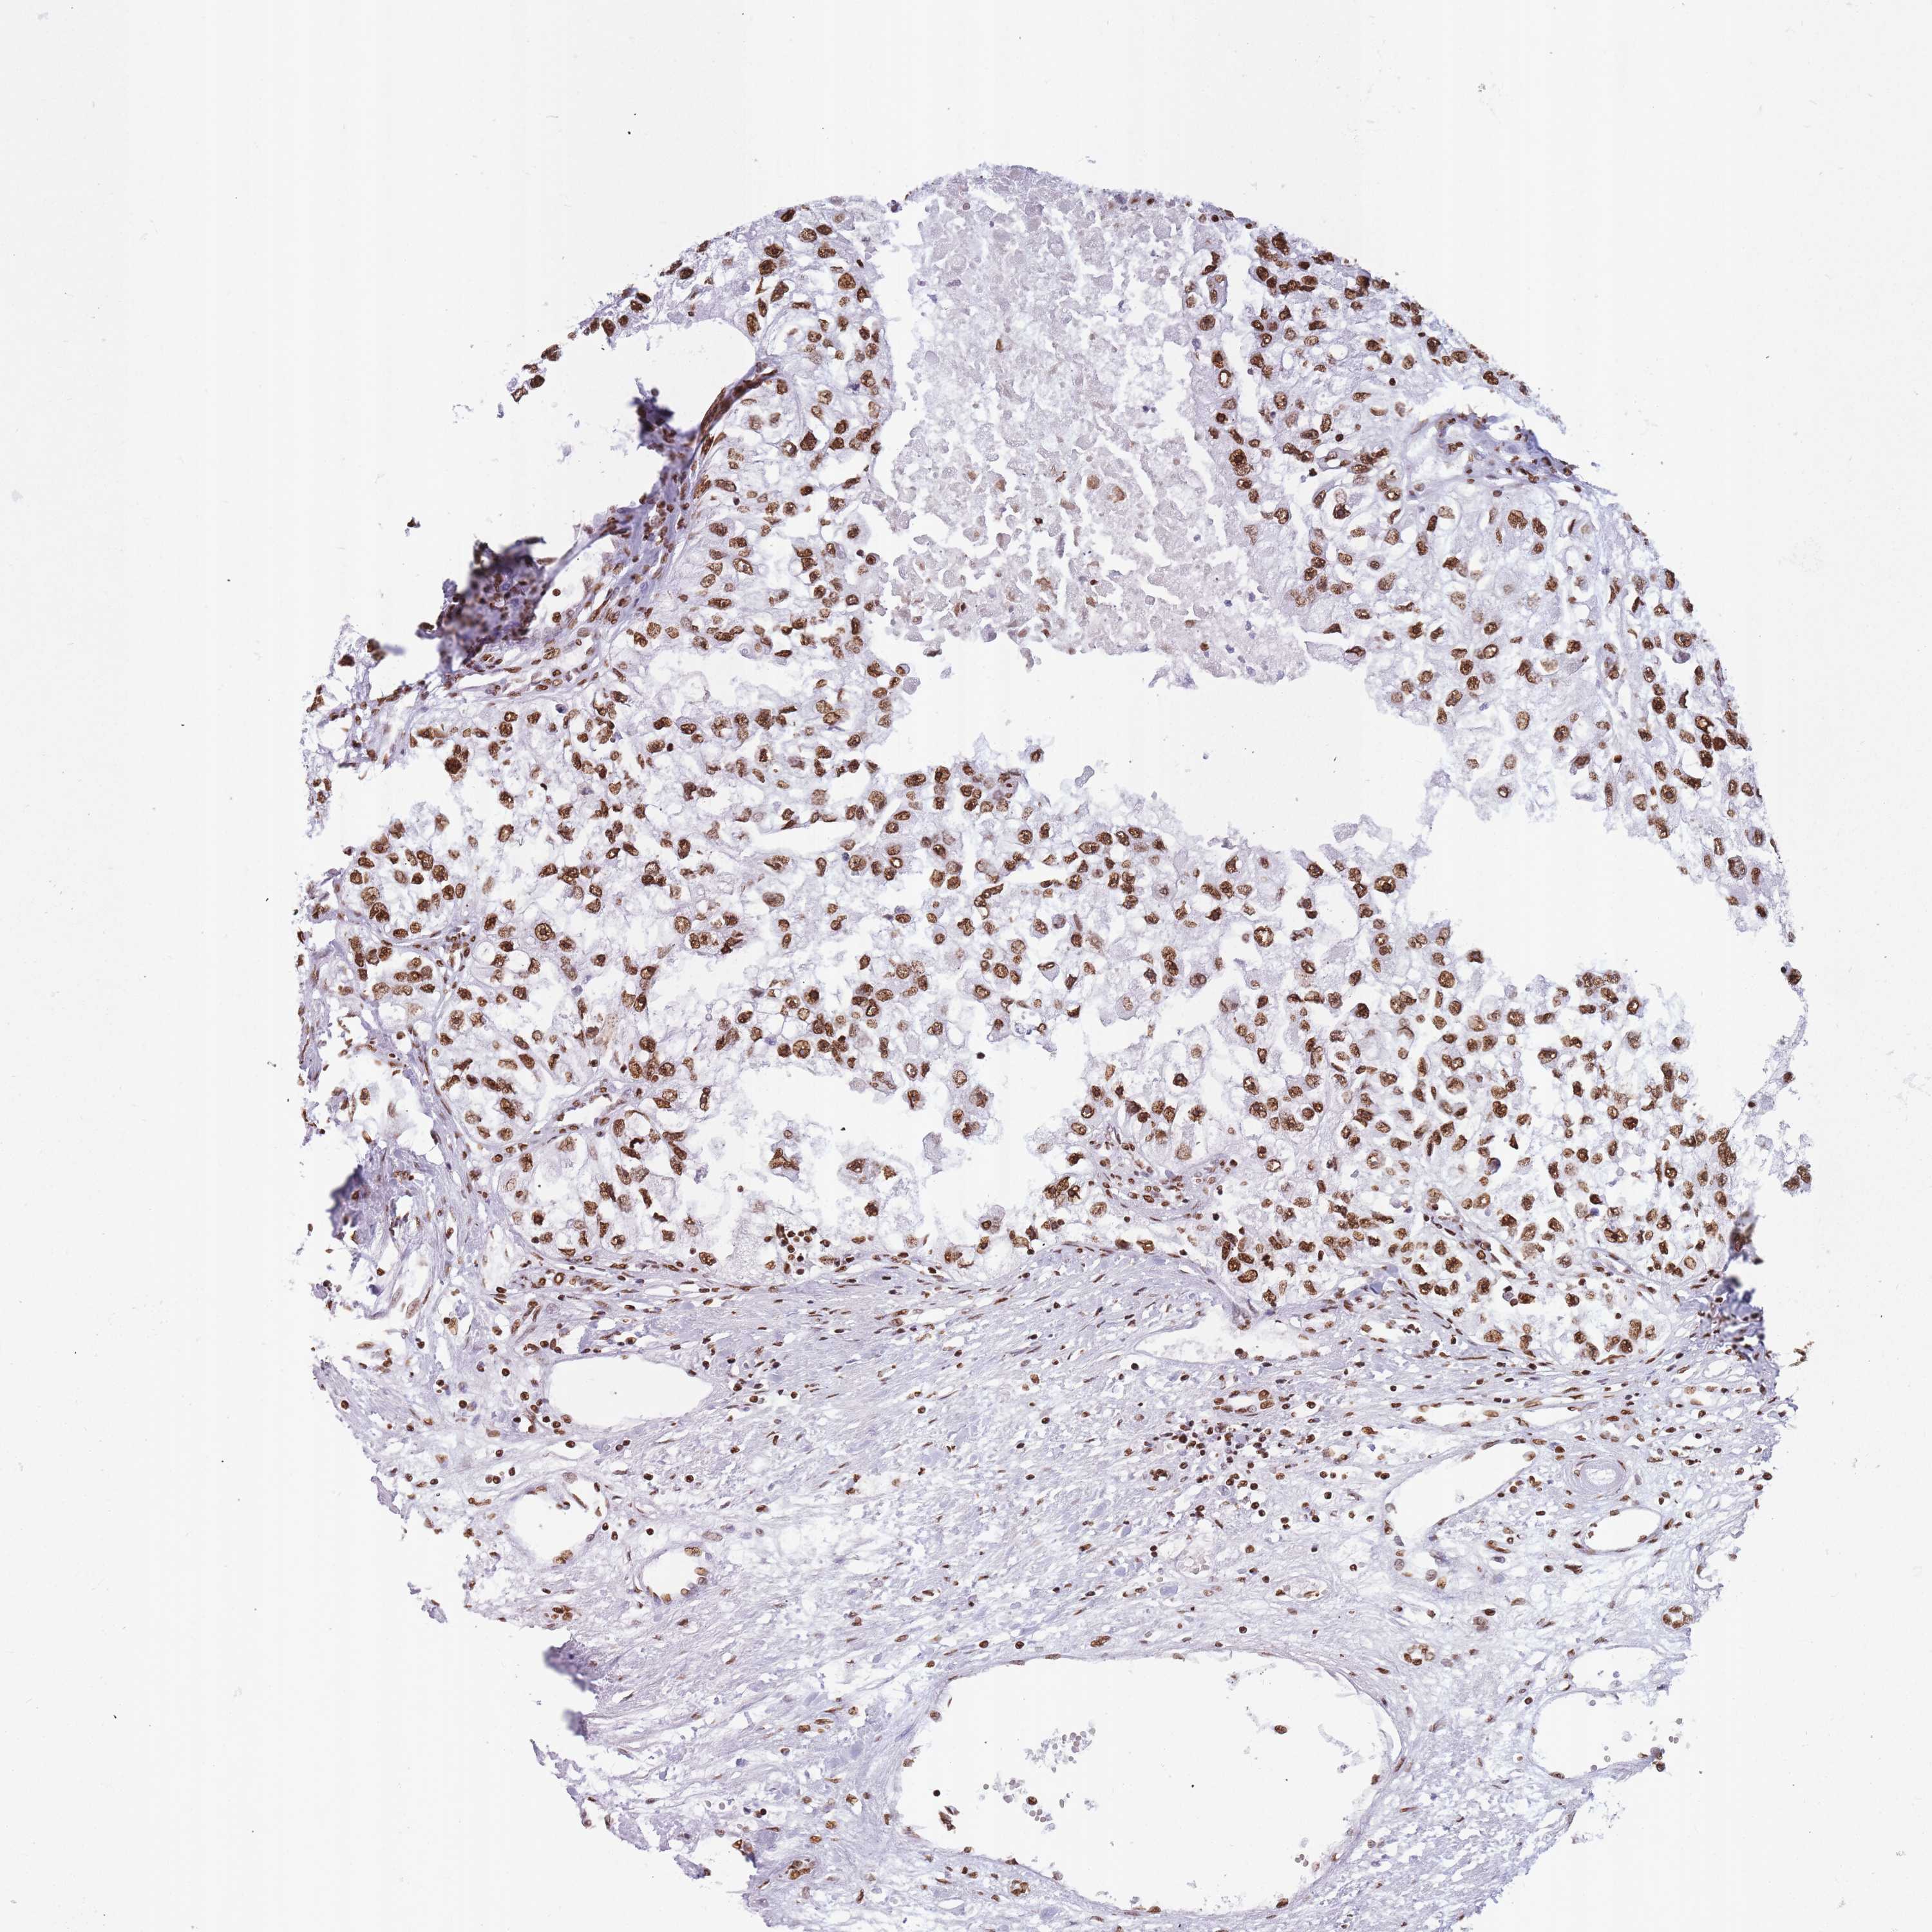

KIDNEY RENAL PAPILLARY CELL CARCINOMA (TCGA) - Interactive survival scatter ploti

The Survival Scatter plot shows the clinical status (i.e. dead or alive) for all individuals in the patient cohort, based on the same data that underlies the corresponding Kaplan-Meier plots. Patients that are alive at last time for follow-up are shown in blue and patients who have died during the study are shown in red.

The x-axis shows the expression levels (FPKM) of the investigated gene in the tumor tissue at the time of diagnosis. The y-axis shows the follow-up time after diagnosis (years). Both axes are complimented with kernel density curves demonstrating the data density over the axes. The top density plot shows the expression levels (FPKM) distribution among dead (red) and alive patients (blue). The right density plot shows the data density of the survived years of dead patients with high and low expression levels respectively, stratified using the cutoff indicated by the vertical dashed line through the Survival Scatter plot. This cutoff is automatically defined based on the FPKM cutoff that minimizes the p-score. The cutoff can be changed by dragging the vertical line or by entering a cutoff value in the square labeled "Current cut-off".

Under the Survival Scatter plot the p-score landscape (black curve; left axis) is shown together with dead median separation (red curve; right axis). Dead median separation is the difference in median mRNA expression between patients who have died with high and low expression, respectively. It is calculated as follows: median FPKM expression of dead patients with high expression - median FPKM expression of dead patients with low expression. This is intended to aid the user in visually exploring custom cutoffs and the associated p-scores and dead median separation.

Individual patient data is displayed and can be filtered by clicking on one or more of the category buttons on the top of the page. Categories describing expression level and patient information include: high, low, alive, dead, female, male and tumor stages. The scale of the x-axis can be toggled between linear and log-scale by clicking on the "x log" button. Mouse-over function shows TCGA ID, patient information and mRNA expression (FPKM) for each patient.

& Survival analysisi

Kaplan-Meier plots summarize results from analysis of correlation between mRNA expression level and patient survival. Patients were divided based on level of expression into one of the two groups "low" (under cut off) or "high" (over cut off). X-axis shows time for survival (years) and y-axis shows the probability of survival, where 1.0 corresponds to 100 percent.

HNRNPUL1 is not prognostic in Kidney Renal Papillary Cell Carcinoma (TCGA)